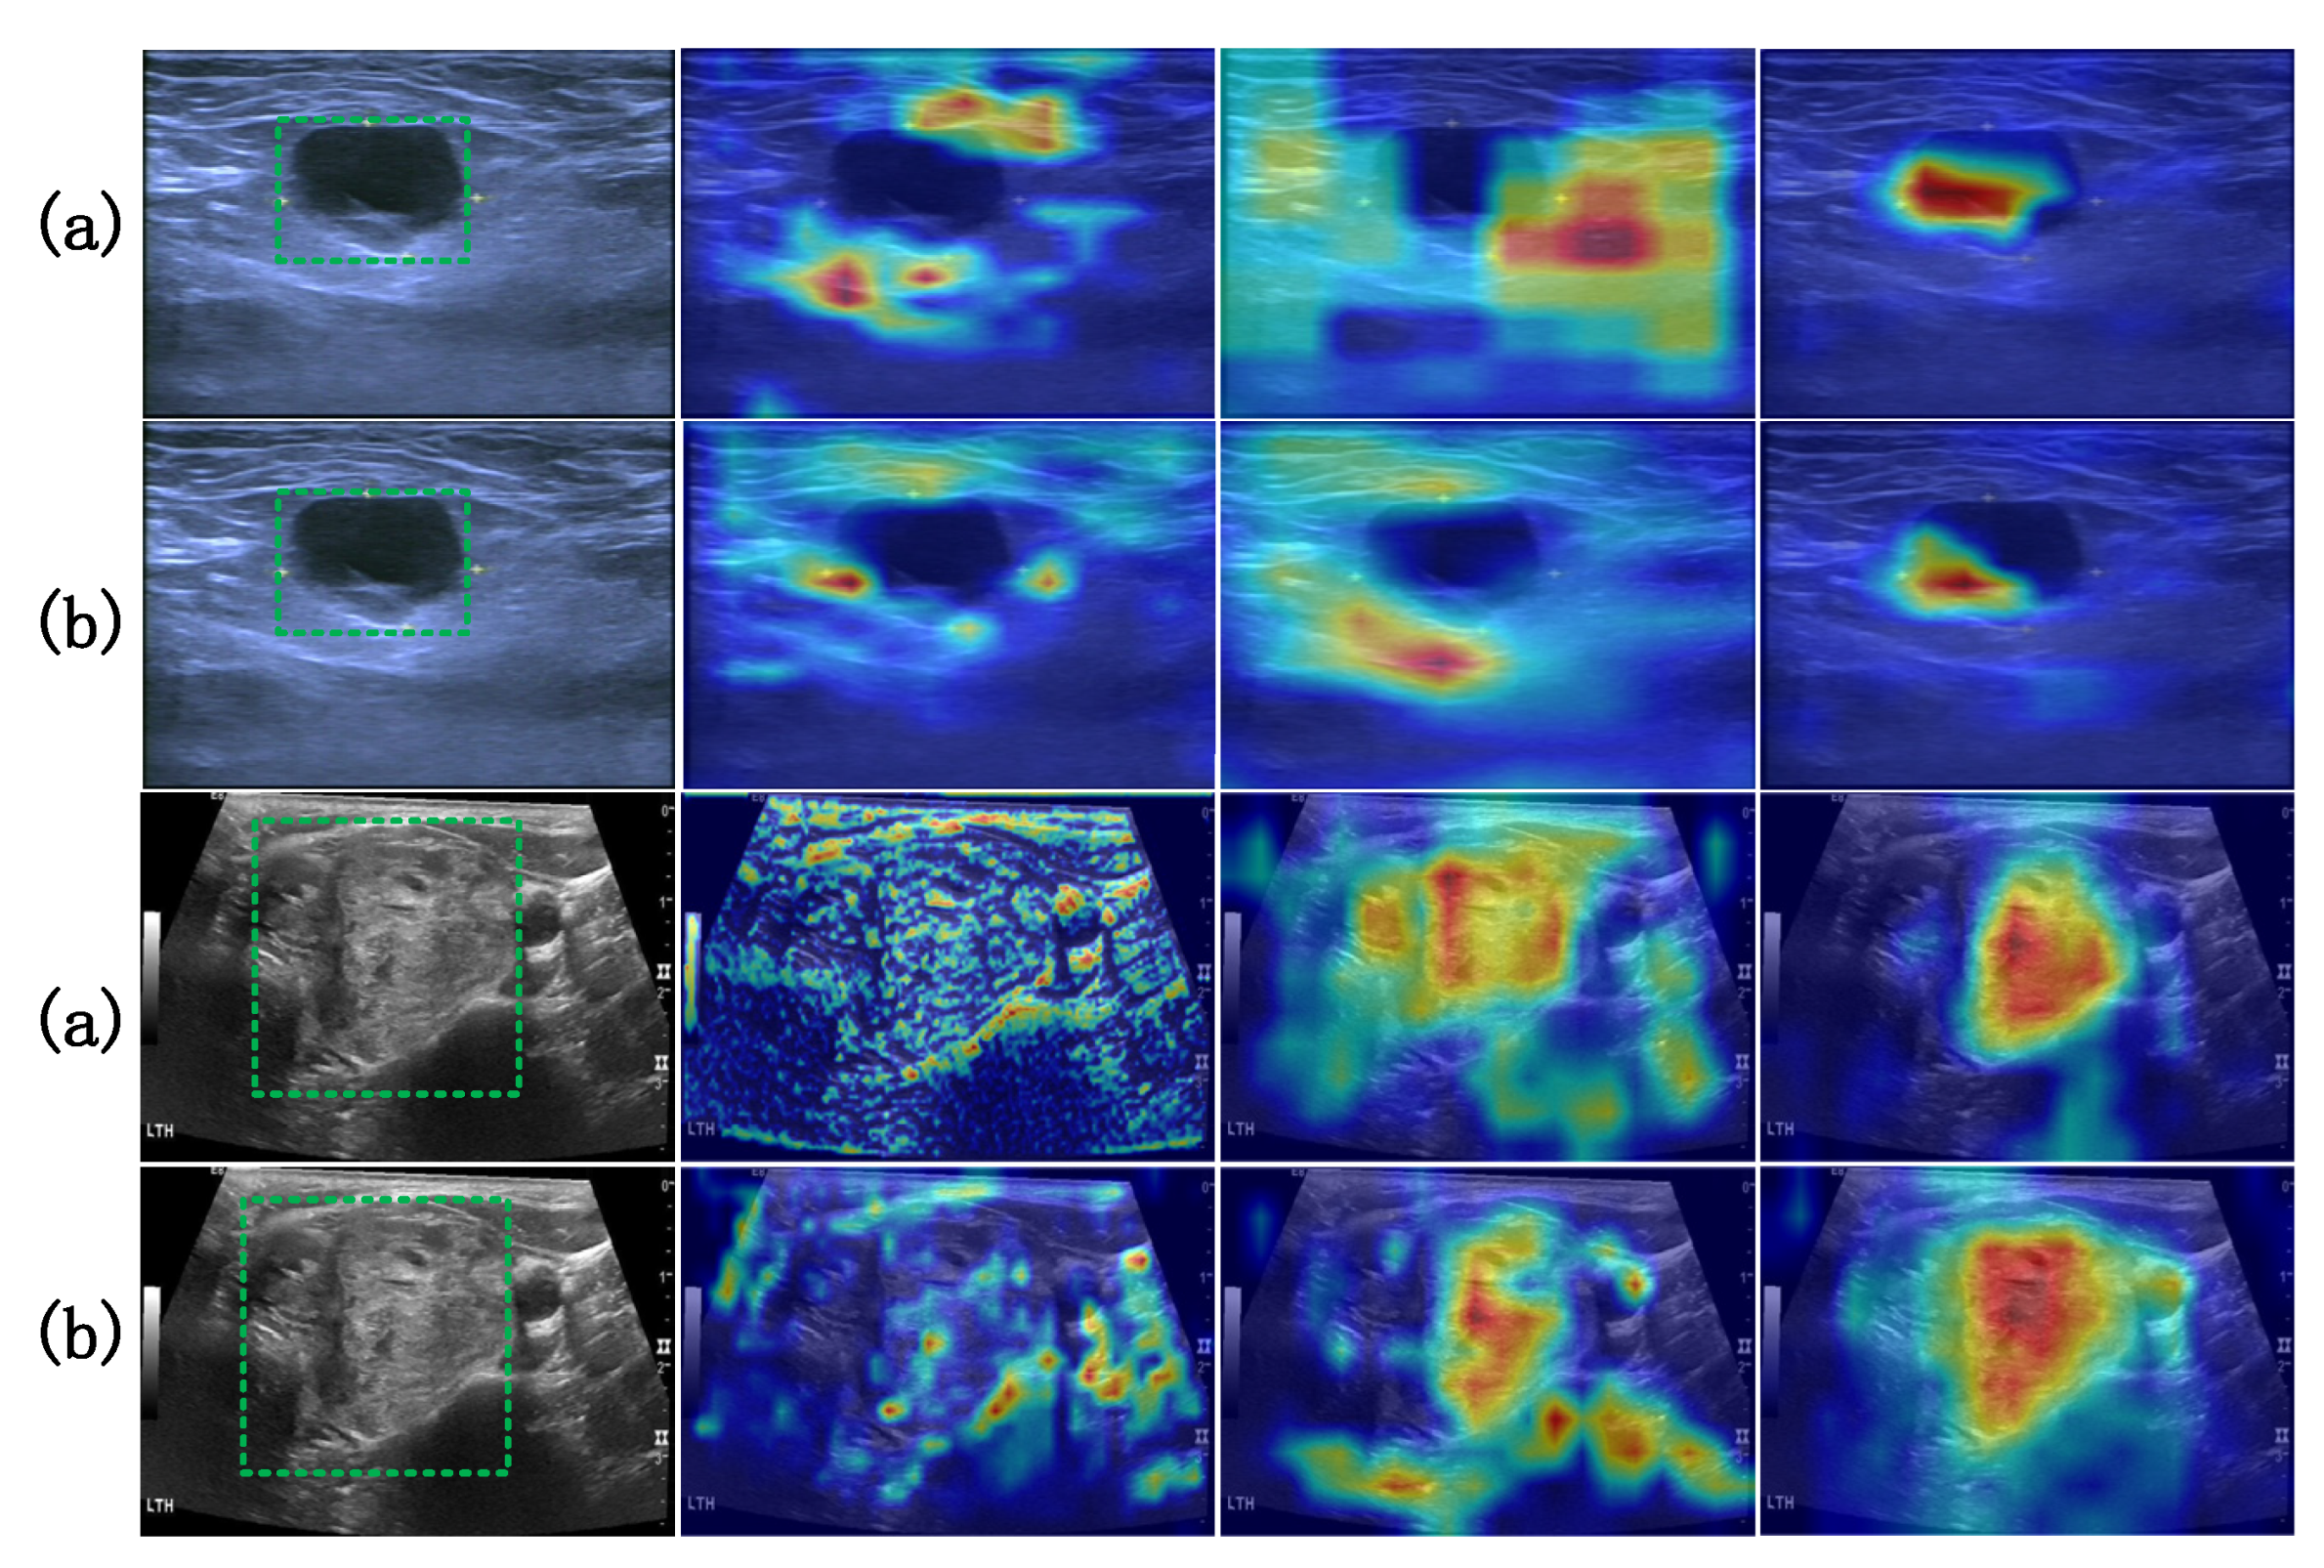

- This paper proposes a collaborative attention mechanism (SAF-Net) that combines channel-wise and spatial feature refinement within a symmetrical dual-branch architecture. Initially, features are filtered through a coarse channel attention process, followed by fine-grained selection of key diagnostic channels. This is subsequently complemented by spatial attention refinement. The collaborative attention structure ensures symmetric calibration of spatial and channel weights, enhancing the model’s focus on the boundaries and echogenic features of thyroid nodules. The guided attention constraint enforces structural coherence, allowing the model to dynamically highlight diagnostically relevant regions and significantly improve small object sensitivity and feature representation quality.

3.4. Collaborative Attention Mechanism SAF-NET Module